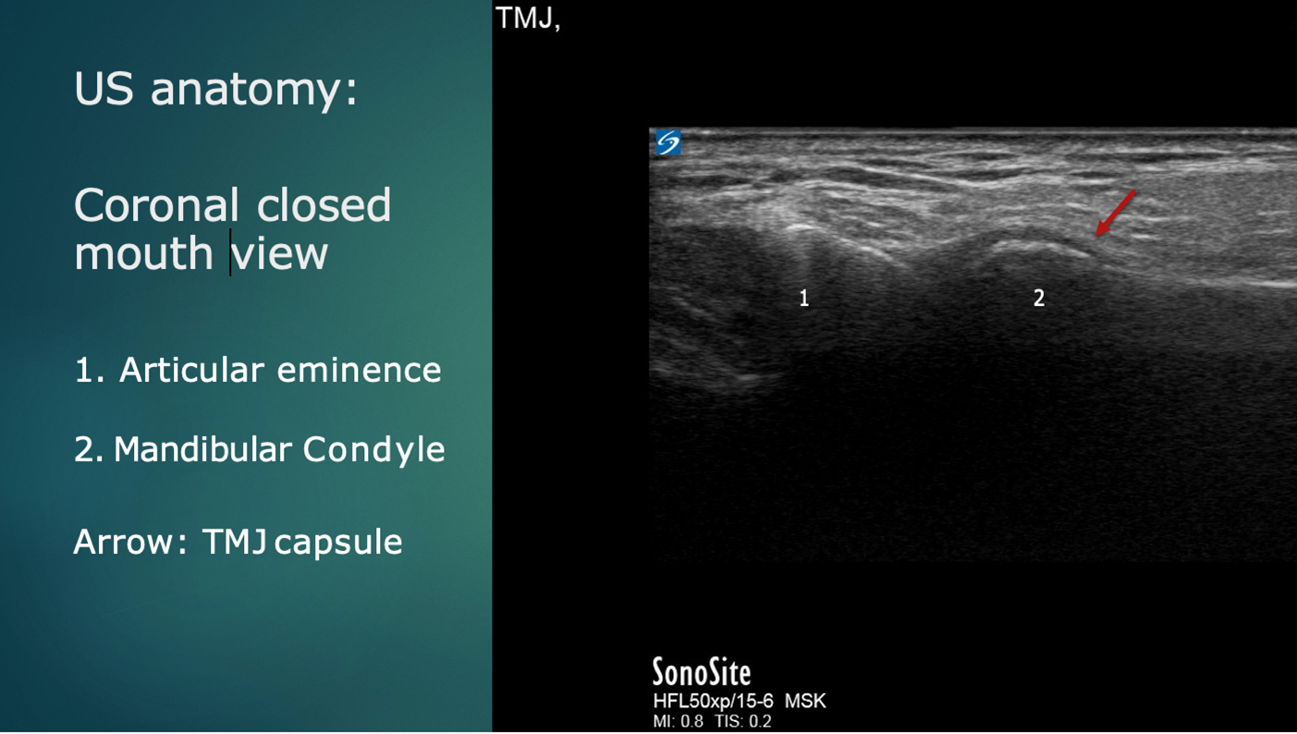

Ultrasound anatomy reveals the mandibular condyle and the articular eminence of the temporal bone. (Figure 4).

Figure 4: Ultrasound anatomy: Coronal plane